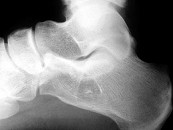

- 单项选择题男,33岁, 无明显症状,结合图像, 最可能的诊断是 ( )

A、骨囊肿

B、骨脓肿

C、未见异常

D、骨內脂肪瘤

E、血管瘤